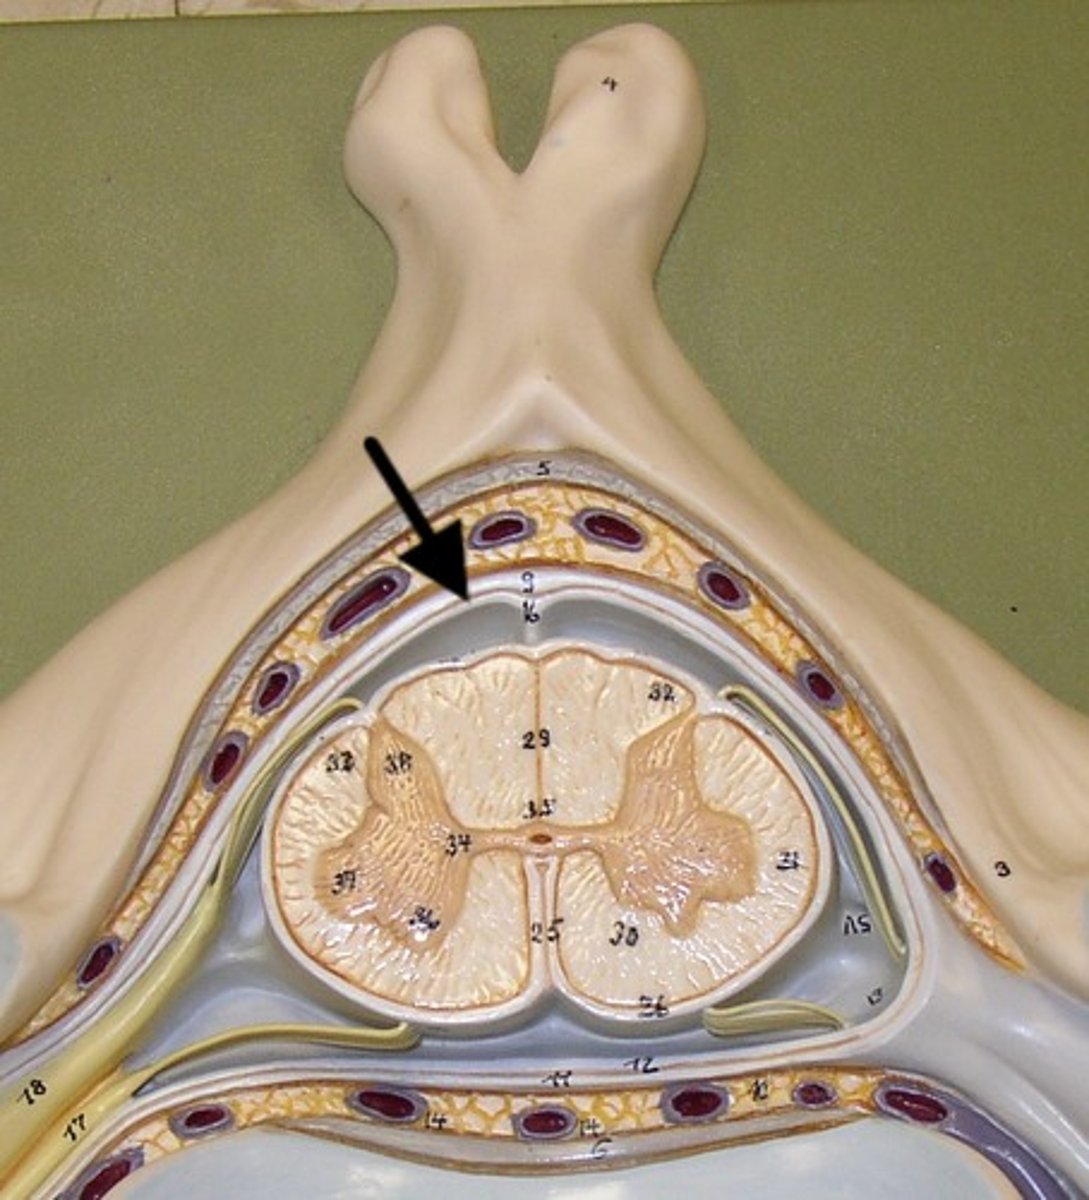

Dura mater

1

arachnoid mater

2

pia mater

3

epidural space

4

subdural space

5

subarachnoid space

6